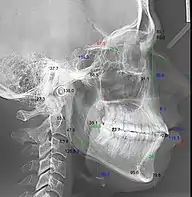

Телерентгенографія з кефалометричним аналізом

Цефалограма — це геометричне змалювання телерентгенограми для вивчення абстрактних закономірностей — кутових і лінійних кефалометричних параметрів.[2][3]